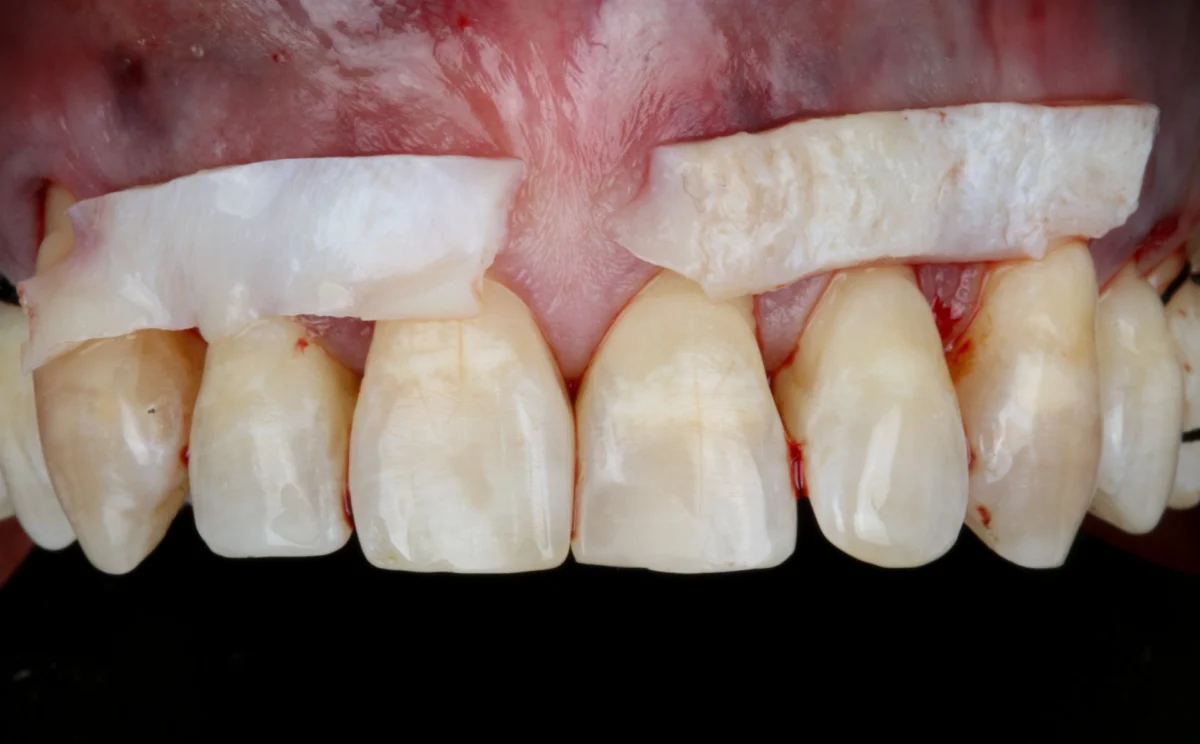

El injerto de encía es un procedimiento quirúrgico destinado a corregir la recesión gingival, es decir, cuando las encías se retraen y dejan expuesta la raíz del diente. Este tratamiento consiste en tomar tejido de una zona donante, generalmente del paladar, o utilizar materiales biocompatibles, para cubrir las áreas afectadas y proteger las raíces expuestas.

El injerto de encía no solo mejora la estética de la sonrisa, sino que también previene la sensibilidad dental y el riesgo de futuras complicaciones como caries radicular o pérdida de hueso. Además, refuerza la estructura de las encías, proporcionando una protección duradera.